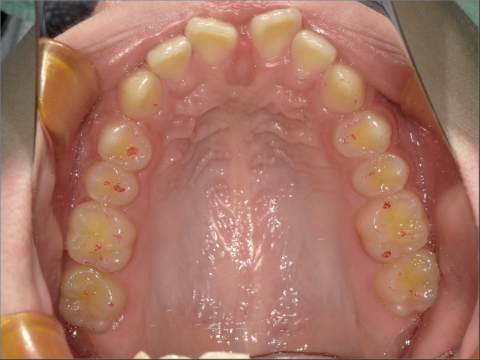

ご年齢 15歳女性 治療期間 2022/07/02〜2023/12/02(1年5ヶ月)

診断 110,000円(税込) アライナー 660,000円(税込) リテーナー 55,000円(税込)

ご年齢 15歳女性

治療期間 2022/07/02〜2023/12/02(1年5ヶ月)

診断 110,000円(税込)

アライナー 660,000円(税込)

リテーナー 55,000円(税込)

BEFORE

AFTER